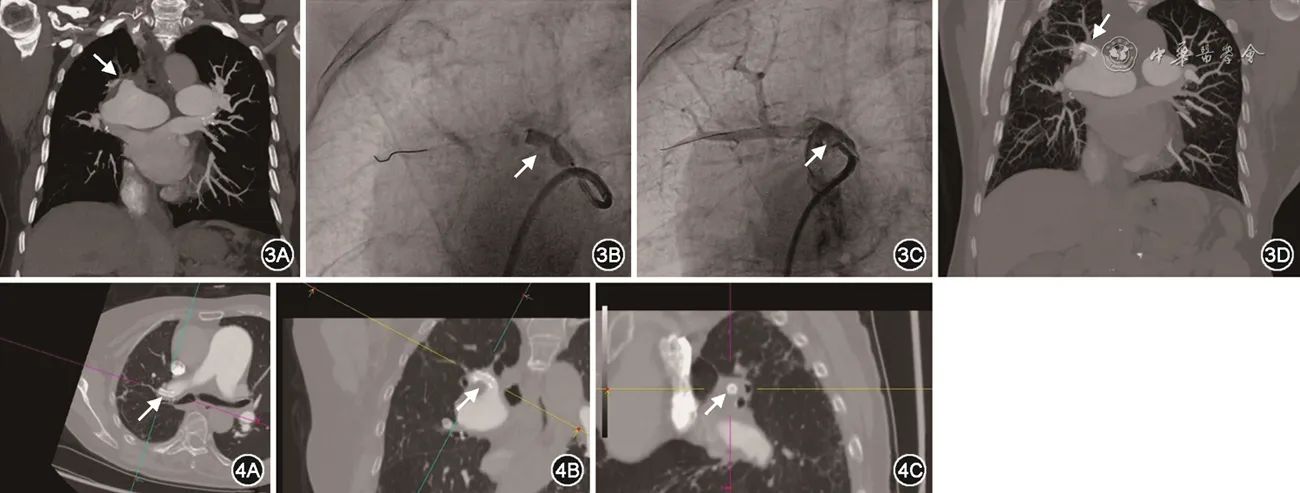

入院后体格检查:体温36.6 ℃,脉搏106次/min,呼吸频率20次/min,血压123/68 mmHg,双肺呼吸音清,未闻及干湿性啰音,心率 106 次/min,律齐,P2>A2,各瓣膜区未闻及杂音,腹软,双下肢中度水肿,双下肢静脉迂曲、扩张,局部皮肤片状色素沉着。辅助检查:心脏彩超示:双房、右室增大,估测肺动脉收缩压89 mmHg,肺动脉高压(重度),二尖瓣、三尖瓣、肺动脉瓣及主动脉瓣反流(轻度),左心室收缩功能未见异常,少量心包积液。CT肺动脉造影(CTPA)示:右肺动脉干及右肺上、中、下多发肺动脉分支完全或不完全性栓塞,肺动脉高压(图3A)。双下肢静脉彩超示:双侧下肢大隐静脉曲张;双侧小腿肌间静脉增宽;双下肢静脉血流通畅。肺通气/灌注显像显示:(1)双肺多发灌注功能受损灶,以左肺上叶尖后段、舌段、下叶前内、外基底段、右肺上叶、中叶及下叶基底段等为著;(2)分肺灌注功能的测定:左肺占全肺的77.43%;右肺占全肺的22.57%。血浆D-二聚体534 ng/ml;NT-proBNP 68.6 pg/ml;进一步查肌钙蛋白、易栓症、同型半胱氨酸、抗核抗体谱、血管炎筛查均未见异常。予右心导管检查提示毛细血管前性肺动脉高压(表2)。肺动脉造影显示:肺动脉多发狭窄,血流缓慢。诊断“慢性血栓栓塞性肺动脉高压”。评估患者状况,考虑患者肺血栓病灶主要位于外周肺动脉,PEA术获益不高,选择BPA治疗。于2021年4月1日行第1次BPA,术后患者气促症状好转、双下肢水肿消退出院。出院带药华法林3 mg,1次/d和利奥西呱2.5 mg,3次/d治疗。2021年5月13日进行第2次BPA治疗,术中行选择性肺动脉造影显示右上叶肺动脉RA3主干狭窄,导丝通过狭窄病变至血管远端,测量狭窄近端压力60/25/38 mmHg,远端压力21/7/15 mmHg,依次使用Boston Scientific 4.0 mm×20 mm、5.0 mm×20 mm、6.0 mm×20 mm于狭窄处扩张,扩张压力为8~10 atm,每次扩张时间10~15 s(球囊工作压范围6~14 atm)。球囊扩张治疗后,造影仍呈束腰状狭窄(图3B),狭窄近端压力58/25/36 mmHg,远端压力22/9/18 mmHg,狭窄两侧压差明显。考虑球囊扩张治疗效果不佳,决定行肺动脉支架植入治疗,球囊预扩张后,将指引导管送入狭窄病变远端,沿导管入Boston Scientific 6.0 mm×18 mm支架1枚至RA3,造影确认支架可覆盖狭窄范围后,10 atm压力扩张释放支架(支架球囊工作压范围8~14 atm)。支架植入后复查造影示支架膨胀良好无明显狭窄,无需后扩张(图3C)。复测支架近端压力55/18/32 mmHg,远端49/16/30 mmHg。术后患者症状明显改善。出院带药:马西替坦10 mg,1次/d,拜阿司匹林100 mg,1次/d和利伐沙班20 mg,1次/d抗凝治疗。2021年6月8日第3次BPA术,肺动脉平均压降至正常。出院停用马西替坦,仅给拜阿司匹林100 mg,1次/d和利伐沙班20 mg,1次/d抗凝治疗。拜阿司匹林100 mg,1次/d共服用3个月后停用,持续利伐沙班20 mg,1次/d抗凝治疗,随访患者无活动困难,状态理想。

图3 例2患者影像结果:图3A为患者CTPA冠状位图像:支架植入前CTPA图像,RA3血管明显狭窄(箭头所示),图3B为RA3主干使用球囊扩张治疗,仍呈束腰状狭窄(箭头所示),图3C为RA3主干支架植入后造影图像,可见狭窄明显改善(箭头所示),图3D为患者支架植入后CTPA图像,可见RA3植入支架(箭头所示),远端血流明显改善

图4 例2患者肺动脉支架植入术后复查CTPA图像清晰显示支架位置及全貌,图4A、B显示支架长轴(箭头所示),图4C显示支架横截面(箭头所示)

支架植入1年后,2022年6月12日患者返院复查右心导管提示肺动脉压力正常,CTPA示:右肺动脉支架植入术后改变,支架通畅(图3D,图4)。行肺动脉造影示:RA3主干支架未见明显充盈缺损、狭窄,远端血流通畅。支架内行光学相干断层扫描技术(OCT)检查提示:支架贴壁良好,支架内见血管内膜覆盖,未见网格样血栓或附壁血栓,血管管腔无狭窄(图5)。